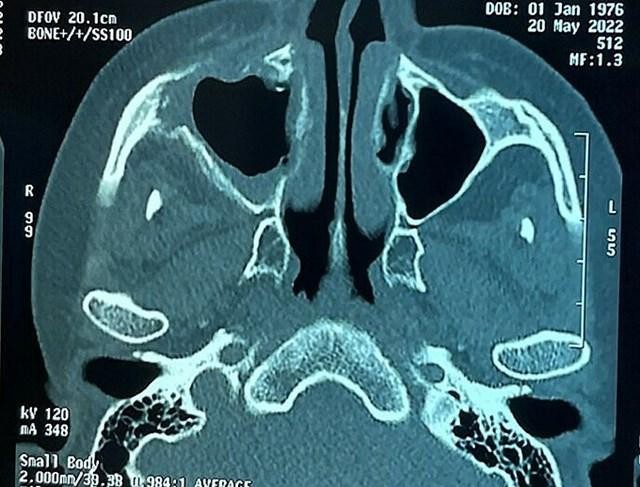

Phim chụp bệnh nhân bị hoại tử xương sọ (Ảnh: Bệnh viện Chợ Rẫy). |

Theo PGS.TS Trần Minh Trường, các bệnh nhân cho biết đau vùng mặt, răng, vòm miệng trong giai đoạn bị nhiễm COVID-19, sau đó tiếp tục tiến triển kéo dài âm ỉ, không giảm. Biểu hiện lâm sàng thường gặp khi bác sĩ khám bệnh là sưng viêm mi mắt; sưng vùng sọ trán; hoại tử xương hàm, răng, xương vòm miệng gây khó nhai; hoại tử nặng hốc mũi lan lên nền sọ. Bệnh có một số dấu hiệu giống viêm xoang nên dễ chẩn đoán nhầm.

Bệnh cốt tủy viêm xương nền sọ hiếm gặp hơn, dễ ảnh hưởng tính mạng. Theo RSNA Journals, đây là bệnh nhiễm trùng thái dương, xương cầu hoặc xương chẩm. Bệnh khó chẩn đoán vì các triệu chứng không điển hình, diễn biến lâm sàng kéo dài và hình ảnh chụp X-quang dễ gây nhầm lẫn với các chứng bệnh khác. Bệnh nhân thường có các triệu chứng không đặc trưng như nhức đầu, đau mặt. Hầu hết khởi phát viêm tai ngoài, có biểu hiện đau nhức dữ dội, chảy mủ tai, một số trường hợp nặng dẫn đến mất thính giác. Trong các trường hợp khác, người bệnh bị viêm xoang, dẫn đến nghẹt mũi, chảy nước mũi, nhức đầu và sốt.